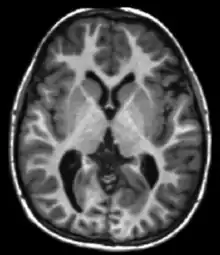

| Spin echo | T1 weighted | T1 | Measuring spin–lattice relaxation by using a short repetition time (TR) and echo time (TE). |

Standard foundation and comparison for other sequences |

Each tissue returns to its equilibrium state after excitation by the independent relaxation processes of T1 (spin-lattice; that is, magnetization in the same direction as the static magnetic field) and T2 (spin-spin; transverse to the static magnetic field). To create a T1-weighted image, magnetization is allowed to recover before measuring the MR signal by changing the repetition time (TR). This image weighting is useful for assessing the cerebral cortex, identifying fatty tissue, characterizing focal liver lesions, and in general, obtaining morphological information, as well as for post-contrast imaging. To create a T2-weighted image, magnetization is allowed to decay before measuring the MR signal by changing the echo time (TE). This image weighting is useful for detecting edema and inflammation, revealing white matter lesions, and assessing zonal anatomy in the prostate and uterus.